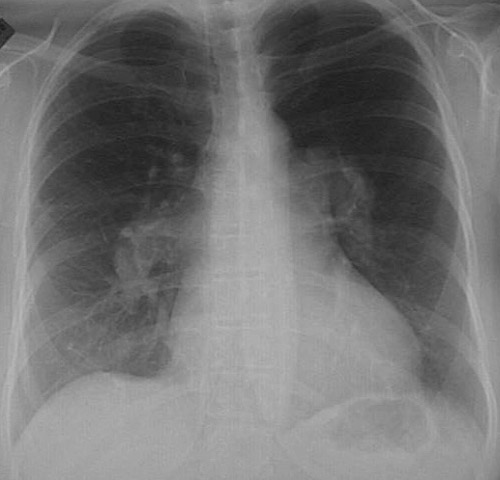

![]() | This chest radiograph demonstrates prominent dilated pulmonary arteries branching from the hila. This patient had the rare condition of primary pulmonary hypertension, without an underlying restrictive or obstructive lung disease to account for the hypertension. |